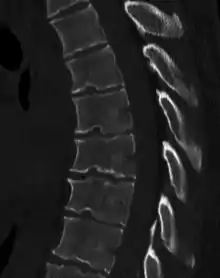

Scheuermann's disease

Scheuermann's disease is a self-limiting skeletal disorder of childhood. Scheuermann's disease describes a condition where the vertebrae grow unevenly with respect to the sagittal plane; that is, the posterior angle is often greater than the anterior. This uneven growth results in the signature "wedging" shape of the vertebrae, causing kyphosis. It is named after Danish surgeon Holger Scheuermann.[3][4][5]

| Scheuermann's disease on lateral Xray of the T spine | |